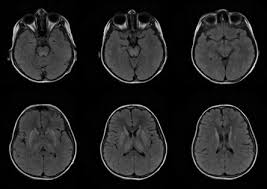

6 8 Neurologic WD is one of the main forms of the disease. In Wilson disease WD T2T2weighted T2w MRI frequently shows hypointensity in the basal ganglia that is suggestive of paramagnetic deposits. It is currently unknown whether this hypointensity is related to copper or iron deposition.

Interval changes on follow-up MR imaging were also closely correlated with clinical findings and. MRI of the brain appears to be more sensitive than CT scanning in detecting early lesions of Wilson disease. The face of the giant panda sign panda sign of the midbrain or double-panda sign is a characteristic pandas face appearance in magnetic resonance imaging MRI images of people with Wilsons disease.

1 In addition a second miniature panda face can be seen in the high signal abnormality in the pons figure C. To describe the spectrum of brain abnormalities in Wilson disease hepatolenticular degeneration as depicted at magnetic resonance MR imaging and computed tomography CT and to relate these findings to neurologic and hepatologic abnormalities.

To describe the spectrum of brain abnormalities in Wilson disease hepatolenticular degeneration as depicted at magnetic resonance MR imaging and computed tomography CT and to relate these findings to neurologic and hepatologic abnormalities. Positive findings believed secondary to this condition were found in 15 subjects. It is found worldwide with a prevalence of approximately 1 case in 30000 live births in most populations. Thirty-eight patients with biochemically proven Wilsons disease underwent magnetic resonanceimaging MRI of the brain as well as neurological examinations. Fifty patients with Wilson disease participated in the cross-sectional. The face of the giant panda sign panda sign of the midbrain or double-panda sign is a characteristic pandas face appearance in magnetic resonance imaging MRI images of people with Wilsons disease. 1 In addition a second miniature panda face can be seen in the high signal abnormality in the pons figure C.